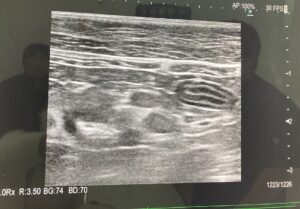

元保護猫あんこ・もなか 多頭飼い嘔吐下痢小腸 シニア猫の嘔吐と下痢・しぶり便…腸管型リンパ腫?膀胱炎?動物病院に駆け込んだ話 2025年12月23日 今年6月、もなかが嘔吐や下痢(便秘?)の症状で急きょ病院へ駆け込んだできごとを書きました。実は最近、また同じような症状が出てしまい、今回は前よりも回復までに時間がかかっています。検査でははっきりした病名がつかず、不安な気持ちと向き合う日々。もしかしたら同じような症状で悩んでいる猫さん、飼い主さんがいるかもしれない。そん... lingo